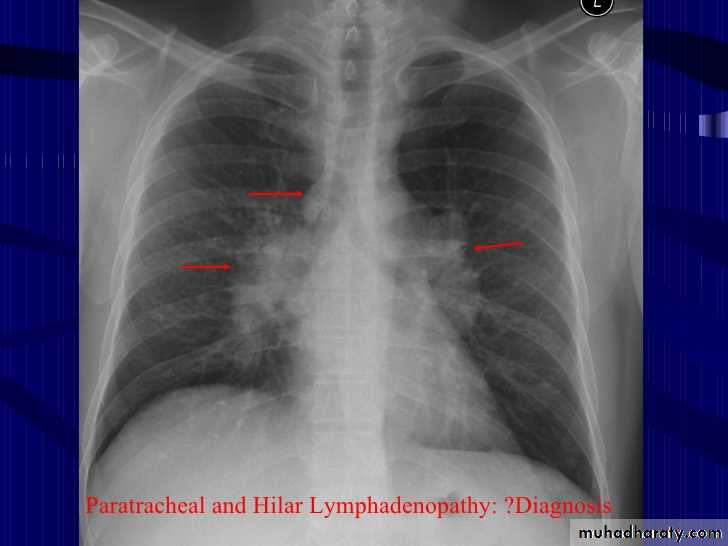

Lymph adenopathy

Bilateral hilar LAP

28.chest XR ( bilateral hilar lymph adenopathy )

29.chest XR ( bilateral hilar lymph adenopathy )